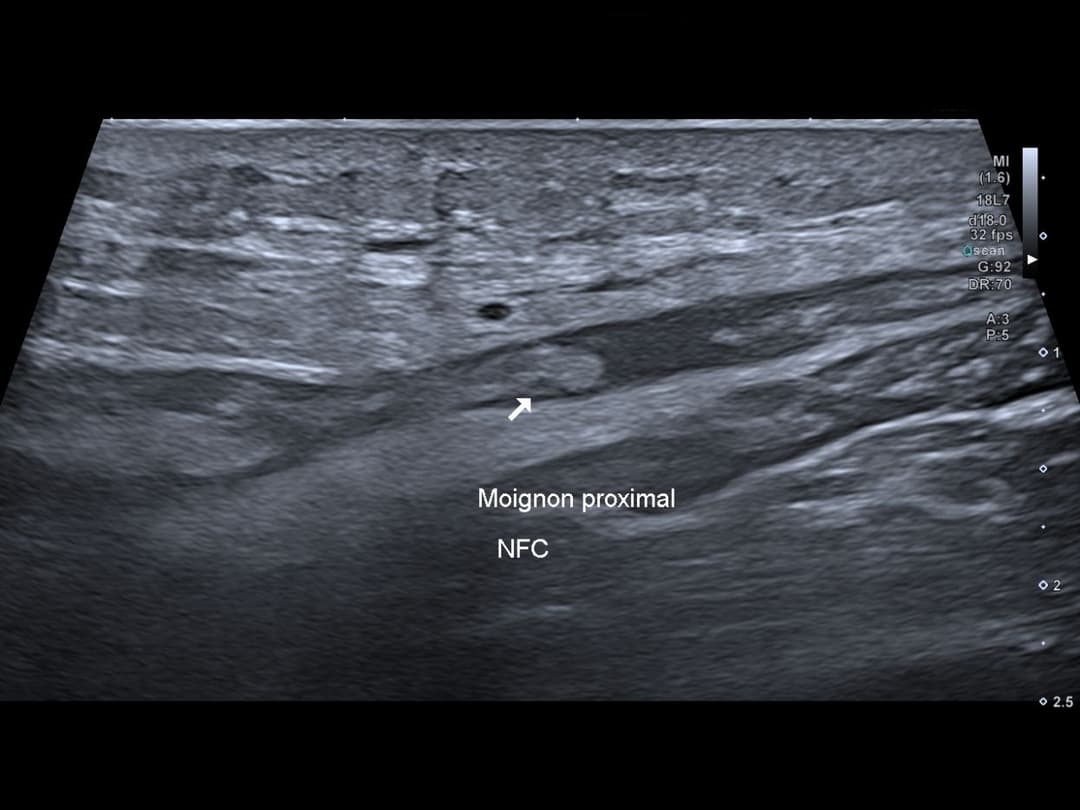

Echographie réalisé avant chirurgie pour marquage du nerf fibulaire commun.

Rupture complète de la continuité du nerf fibulaire commun juste après sa naissance du nerf sciatique, avec un écart interfragmentaire de 4 cm.

Visualisation du moignon proximal du NFC